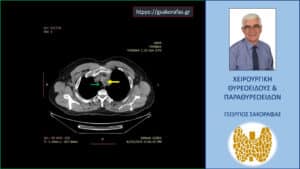

Αξονική τομογραφία – απεικόνιση σε εγκάρσια διατομή σε ένα αρκετά χαμηλό επίπεδο στον θώρακα. Το χαμηλότερο σημείο του καταδυόμενου αριστερού λοβού (κίτρινο βέλος) και η σχέση του με την τραχεία (πράσινο βέλος) και τον οισοφάγο (κόκκινο βέλος).